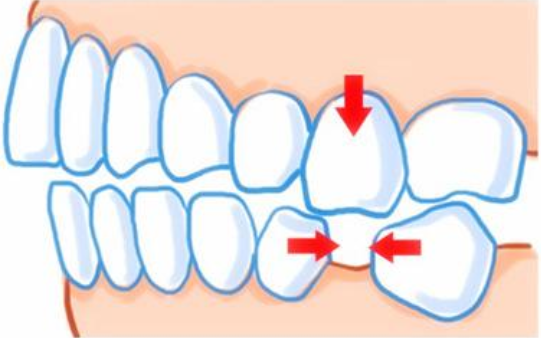

дкЪЕМЪЩњЛюжаЃЌЛЙДцдкзХСэЭтвЛжжШЯЪЖЃЌФЧОЭЪЧаэЖрЛМепШЯЮЊжЛвЊЪЧзьРяЕФбРГнЃЌВЛЙмЦЦЛЕЕНЪВУДГЬЖШЃЌжЛвЊЛМбРУЛгаЭбТфОЭШЋВПвЊБЃСєЃЌМДЪЙВЛФмгУвВВЛПЯАЮЁЃЩѕжСгаЕФЛМепЃЌдкбРГнвбОЭбТфЕФЧщПіЯТЃЌШдШЛАбЛМбРВхЛигЩШтбПзщжЏзщГЩЕФбРЮбФкЁЃетбљзіЪЧЗёПЩааФиЃПгІИУШчКЮОіЖЈЛМбРЪЧЗёБЃСєФиЃПЁЗЁЗЁЗЭЦМідФЖСЃКдкРШЗЛЃЌЪВУДЪБКђАЮжЧГнКУЃП

дкЪЕМЪЩњЛюжаЃЌЛЙДцдкзХСэЭтвЛжжШЯЪЖЃЌФЧОЭЪЧаэЖрЛМепШЯЮЊжЛвЊЪЧзьРяЕФбРГнЃЌВЛЙмЦЦЛЕЕНЪВУДГЬЖШЃЌжЛвЊЛМбРУЛгаЭбТфОЭШЋВПвЊБЃСєЃЌМДЪЙВЛФмгУвВВЛПЯАЮЁЃЩѕжСгаЕФЛМепЃЌдкбРГнвбОЭбТфЕФЧщПіЯТЃЌШдШЛАбЛМбРВхЛигЩШтбПзщжЏзщГЩЕФбРЮбФкЁЃетбљзіЪЧЗёПЩааФиЃПгІИУШчКЮОіЖЈЛМбРЪЧЗёБЃСєФиЃПЁЗЁЗЁЗЭЦМідФЖСЃКдкРШЗЛЃЌЪВУДЪБКђАЮжЧГнКУЃП